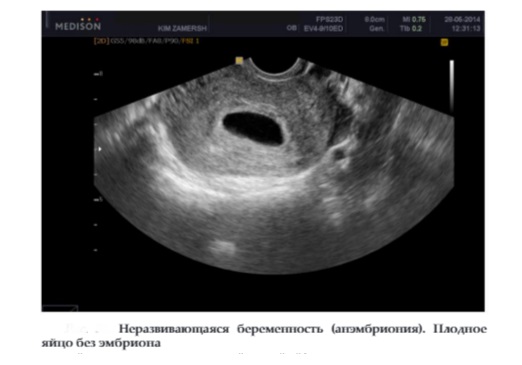

Анэмбриония почему

Анэмбриония почему 116 фотографий